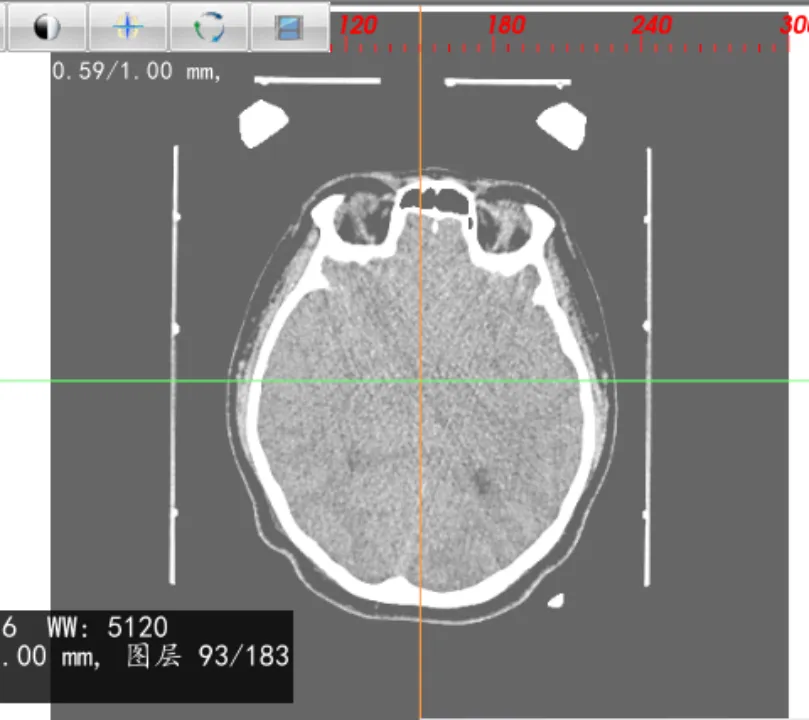

图像融合

导入多个序列,可对图像进行一键融合,生成融合序列,如:进行CT、磁共振融合,设定融合比例,可对CT或磁共振显示的权重进行调整。

0% 50% 100%